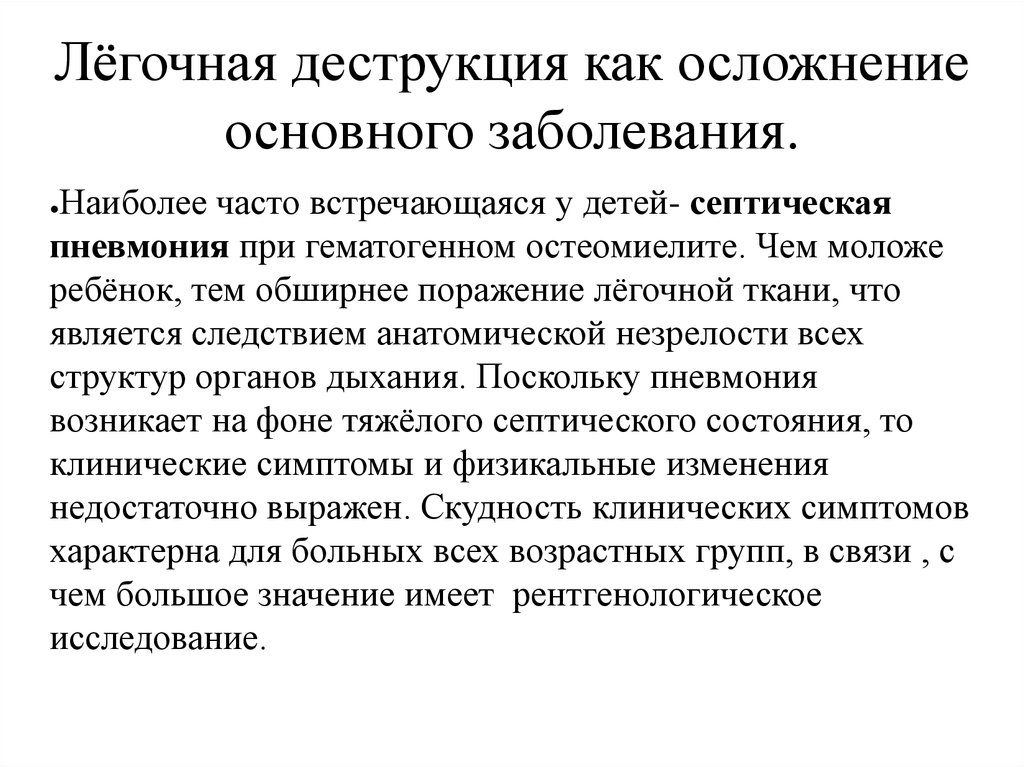

Бактериальная деструкция легких у детей презентация - 88 фото